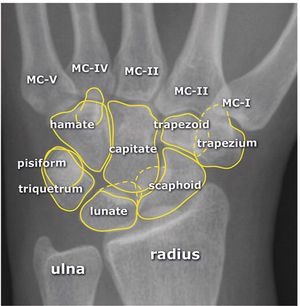

X-ray carpal bone

Anatomy

Xray

Bone